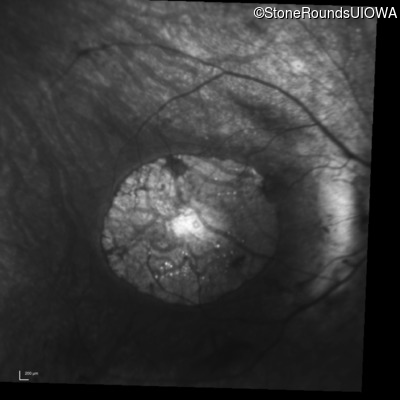

Infrared Fundus Photograph - Right - 10/160 +1

Exemplar